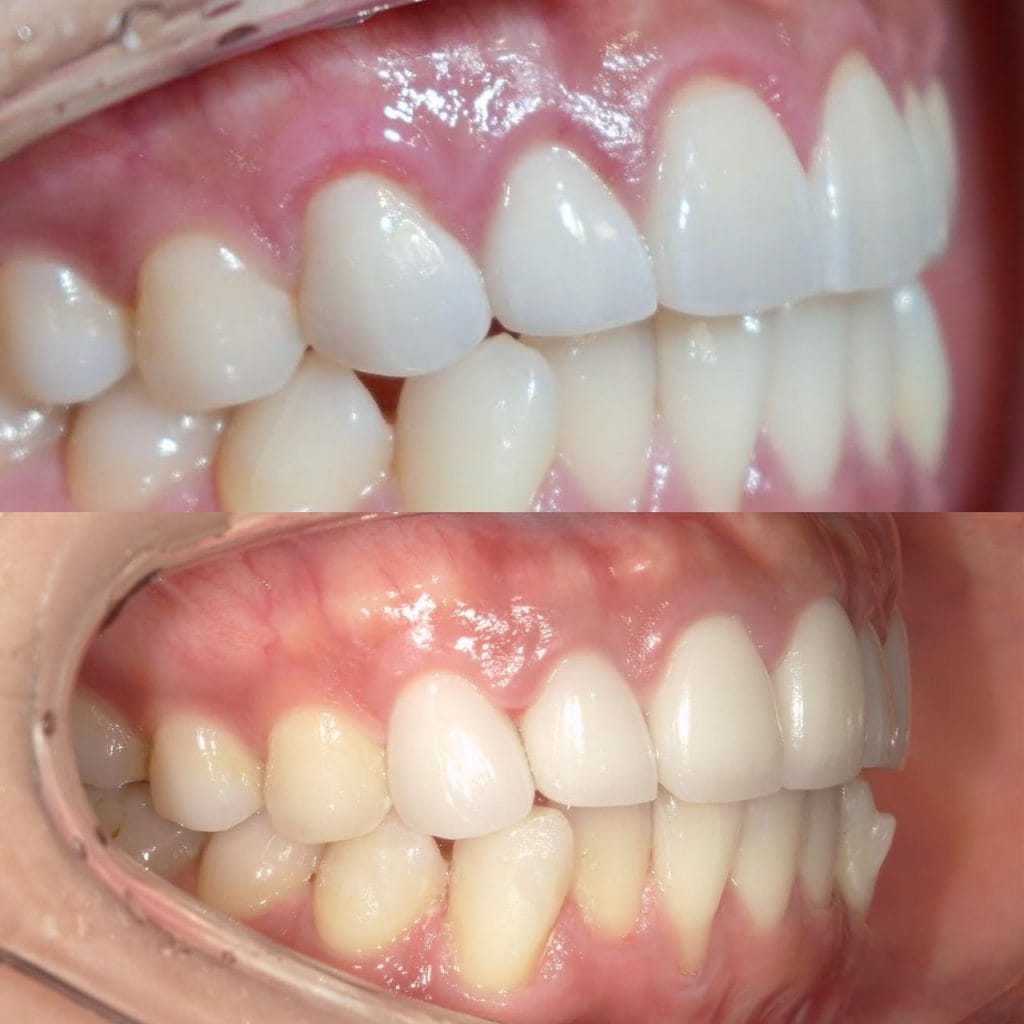

Case033

前歯が虫歯なのと、保険のプラスチックで大きく治療されていて色が悪いこと、歯並びが出っ歯気味であることを気にしてセラミックにしたいという主訴で来院された患者様です。

虫歯が大きかったところは神経治療をきちんと行い、

初診時を含めてトータル4回のご来院で完了です。

今回は前歯を下げる、歯列を整える、白すぎず自然に綺麗に見える色というご希望に沿って治療しました。

ご興味のある方はいつでもご相談ください。

担当 理事長 佐藤 悠野